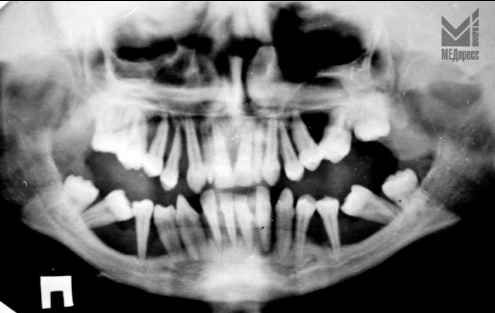

| Рис. 1. Генерализованная атрофия десневого края. Десна бледного цвета, глубокие пародонтальные карманы. Зубы подвижны. |